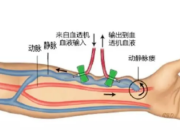

会议快讯汕头市中心医院李绪城主任主持开幕2025年10月19日,由汕头市医学会主办,汕头市医学会血液净化专委会、汕头市血透质控中心及汕头市中心医院联合协办的“第八届粤东地区血液净化治疗新进展研讨班暨第七届汕头市血透质控论坛暨2025年汕头市医学会血液净化专委会学术年会”在汕头国厦万豪酒店成功举行。本次盛会汇聚了粤东地区血液净化领域的众多医护精英,为促进区域学术交流与技术提升留下了精彩的一页。会议围